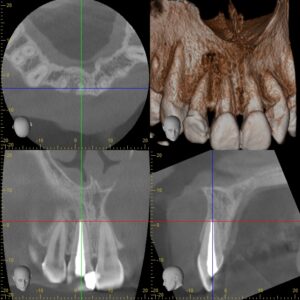

初診時CT画像。根尖部に境界明瞭な直径1㎝ほどの黒いX線透過像を認める。虫歯治療後の歯髄壊死および根尖性歯周炎と診断し、感染根管治療を行うこととした。

同CT画像。根尖部のX線透過像は完全に消失し、骨が再生し完治している。難治性の根尖病巣であっても、必ずしも歯根端切除が必要ではないことが分かる。